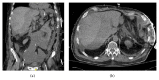

The hemodynamic compromise caused by a large aspirated food particle in the airway can become the focus of medical attention and a distraction from rare but fatal Heimlich maneuver related injuries after an incident of food aspiration. We herein present a case of an 84-year-old man who was brought to the emergency department after an episode of choking at a restaurant followed by several failed Heimlich maneuver attempts. Despite relieving the airway obstruction by extracting a large piece of steak from the airway, the patient remained hypotensive and required continued hemodynamic support. Repeated laboratory tests within 24 hrs of aspiration showed a significant decline in the hemoglobin level. A computed tomography (CT) scan of the abdomen and pelvis showed a lacerated liver with a large subcapsular hematoma draining into the pelvis. Conclusion. Hepatic rupture is a rare complication of Heimlich maneuver; this paper represents the second case report in the literature. It emphasizes the necessity of early identification and surveillance of fatal Heimlich maneuver complications in a high risk population.